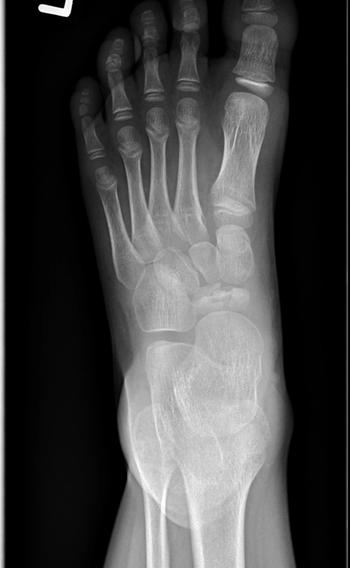

What is your diagnosis for a pediatric patient who presents with findings on a foot radiograph?